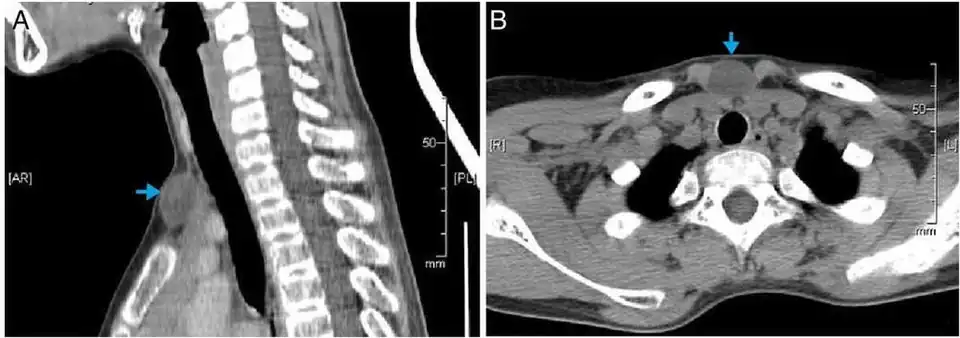

CT scan, showing a homogenous hypodense volume (unspecific cyst-like) CT scan, showing a homogenous hypodense volume (unspecific cyst-like)